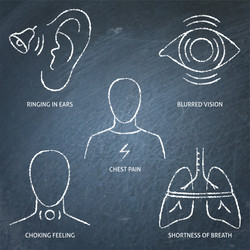

- Nervous

- Tremor

- Attack

- Chalkboard

- Icon

- Panic

- Set

- Dying

- Fear

- Heartbeat

- Numbness

- Sign

- Stress

- Symbol

- Symptom

- Trembling

- Vector

- Anxiety

- Disease

- Disorder

- Illness

- Mental

- Anxious

- Depression

- Distress

- Phobia

- Pulse